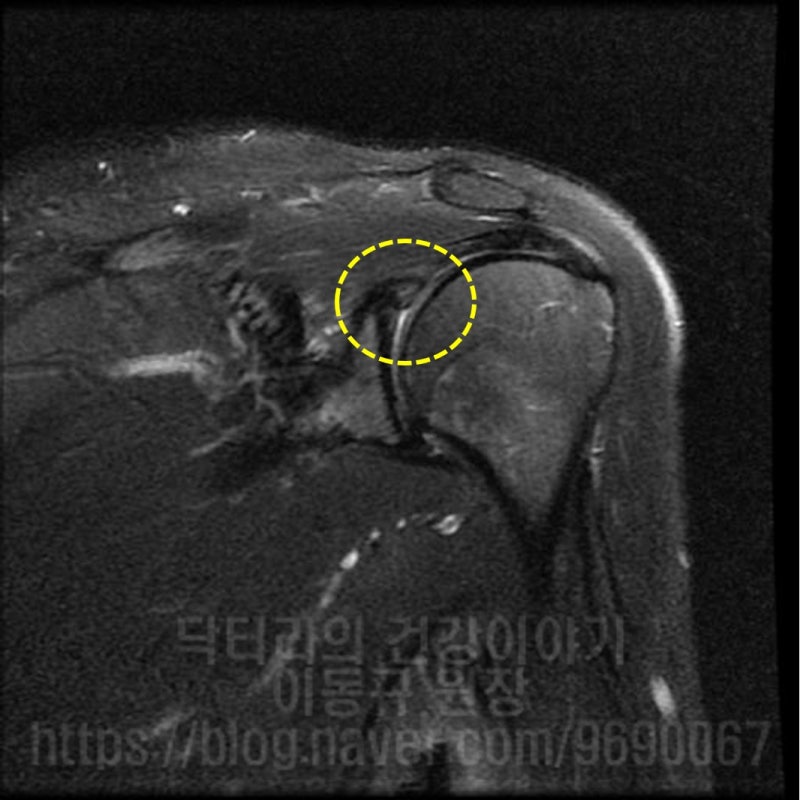

석회성 건염은 매우 통증이 심한 질환입니다. 대부분 회전근개 내에 발생되는 경우가 많습니다. 힘줄에 발생하게 되면 해당 힘줄을 움직일때 마다 극심한 통증을 유발하게 됩니다. 그런데 이러한 석회성 건염이 힘줄이 아닌 다른 곳에 발생된다면 어떨까요? 이번 케이스는 43세 여자 환자 분으로 평상시 피트니스 모델 및 대회를 나갈 정도로 운동을 활발히 하시는 분입니다. 2년전부터 어깨 통증이 발생되고 어깨 후방, 어깨 죽지로 통증이 심하게 있었던 분입니다. 마치 증상이 목 디스크로 인한 연관통 처럼 보이기도 하고 흉곽터널증후군 처럼 보이기도 합니다. 환자는 타 병원에서 목, 어깨 MRI 까지 촬영을 했지만 특별한 진단을 받지 못하고 경추부 문제 정도로 보인다는 이야기를 듣고 주사치료 및 도수치료만 받아오셨던 분이었습니다. 하지만 증상의 호전이 보이지 않고 점점더 통증이 심해지고 근력이 약해져서 저한테 내원하셨던 분이었습니다. 우선 이학적 검사를 해 보았습니다. 특별히 이학적 검사상 특이 소견을 보이지는 않았으나 biceps load test, O'brien test, E/R test 양성 소견을 보였습니다. 즉, 관절와순 병변이 의심되는 소견이었습니다. 가지고 온 영상 자료를 살펴 보겠습니다.

경추부 X-ray 와 MRI 도 확인했으나 특이소견은 없었습니다. 즉 이 환자분은 조금 특이한 위치에 석회가 있으면서 어깨 통증을 유발된 환자고 위치적으로 상견갑신경과 비슷한 위치에서 염증을 일으키다 보니 경추부 문제로 오진되어 치료를 제대로 받지 못했던 경우로 판단됩니다. 위치적으로 뉴핌스치료(석회분쇄흡입술)을 할 수 없는 위치이며 상부관절와순 손상에 대한 치료를 동시에 하기 위해 수술적 치료를 결정하였습니다.